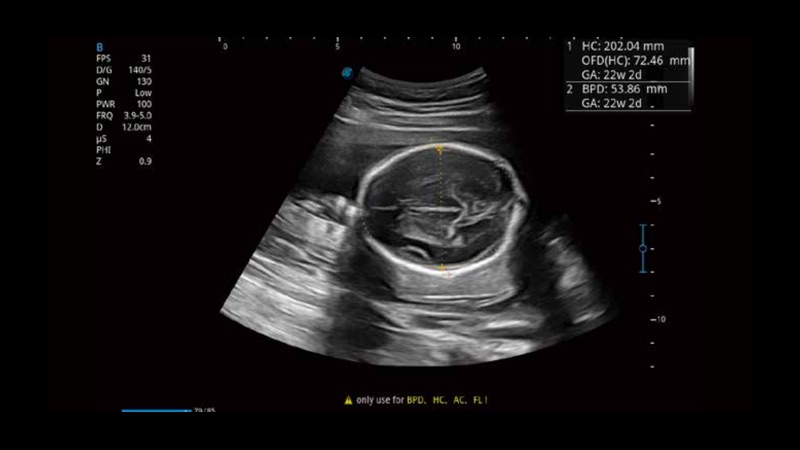

S-Fetus基于大數(shù)據(jù)深度學(xué)習(xí)算法,能夠幫助您在產(chǎn)前篩查過程中智能識別胎兒標(biāo)準(zhǔn)切面、自動測量并錄入報告。一個按鍵,即可智能、精準(zhǔn)、高效地獲取胎兒生理指標(biāo),極大簡化您的產(chǎn)科檢查操作。

可快速對產(chǎn)科掃查切面完成胎兒生理學(xué)參數(shù)的自動測量,減少操作者按鍵次數(shù),大幅提升檢查效率。